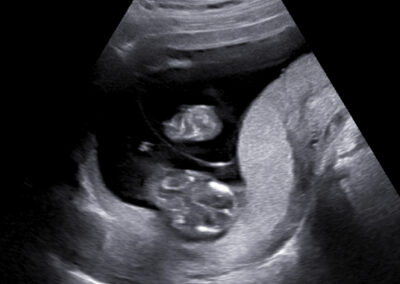

Dear future mother, we provide both basic and specialized ultrasound scans in pregnancy. We use Samsung’s state-of-the-art ultrasound systems and all our doctors are holders of Fetal Medicine Foundation certificates for all types of ultrasound examinations in pregnancy. We follow FMF protocols for fetal examinations and combine 2D with 3D ultrasound scan and assess even subtle anatomical details in order to obtain as precise a result as possible. Throughout the scan, we will keep you informed about the parts of fetal anatomy displayed on the screen. After the scan we will explain to you the results, prognosis and possible further management.

Our ultrasound scans are totally safe both for you and your baby.